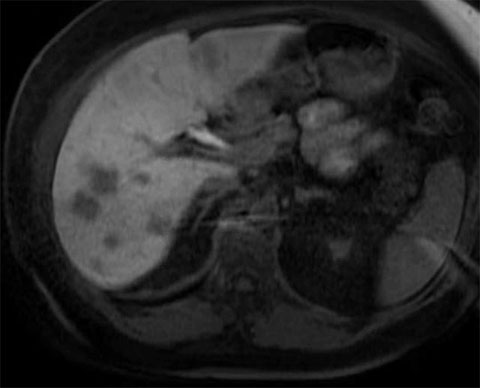

Post-first-surgery MRIs

In the following order, we used microwave ablation the following lesions: lesions 10 on the middle hepatic vein, lesion 9 in segment 4B, lesion 3 in segment 2, lesions 2 and 5 in segment 3, then lesion 4.

We then proceeded with resection of the following lesions in this order: partial hepatectomy of lesion complex 8, partial hepatectomy of lesions 6 and 7, and a wedge resection lesion 11. When we encountered the caudate lesion, it was superficial and would be too difficult to retract; instead, we performed an ablation on it instead.

All of the lesions showed signs of extensive regression from chemotherapy.